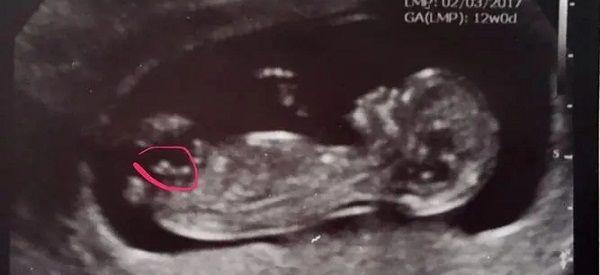

nub点看男女的诀窍是什么准不准?

孕期一直对猜宝宝性别特别有兴趣,但我本身一点儿都不重男轻女,我想要男宝宝,而老公想要女宝宝,都属于异性相吸,但在孕期做检查后医生并没有告诉我胎儿是男还是女,我想..